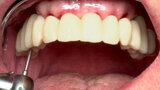

The fully digital Pro Arch protocol